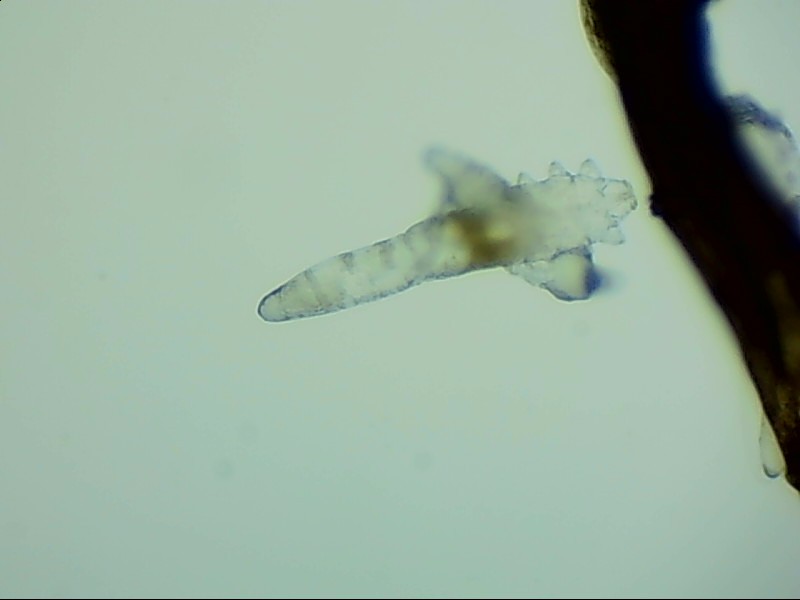

蠕形螨完全長(zhǎng)大也只有0.1-0.2毫米,因此肉眼難以看到它們,只有在電子顯微鏡下我們才能看到睫毛根部的一只只蠕形螨。這些螨蟲(chóng)每天都很活躍,且繁殖速度極快,完成一代生活史僅需大概15天。

螨蟲(chóng)無(wú)所遁形,螨蟲(chóng)鏡檢:

螨蟲(chóng)鏡檢主要是通過(guò)顯微鏡觀察,它能無(wú)死角放大你的睫毛,讓螨蟲(chóng)無(wú)處可躲。

在檢查的時(shí)候,醫(yī)生要在每個(gè)眼瞼上拔出幾根比較典型的睫毛,然后放在光學(xué)顯微鏡下,尋找有沒(méi)有螨蟲(chóng),同時(shí)觀察螨蟲(chóng)的數(shù)量多少。